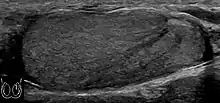

Patients with testicular lymphoma are usually old aged around 60 years of age, present with painless testicular enlargement and less commonly with other systemic symptoms such as weight loss, anorexia, fever and weakness. Bilateral testicle involvements are common and occur in 8.5% to 18% of cases. At sonography, most lymphomas are homogeneous and diffusely replace the testis [Fig. 7]. However focal hypoechoic lesions can occur, hemorrhage and necrosis are rare. At times, the sonographic appearance of lymphoma is indistinguishable from that of the germ cell tumors [Fig. 8], then the patient's age at presentation, symptoms, and medical history, as well as multiplicity and bilaterality of the lesions, are all important factors in making the appropriate diagnosis.

Fig. 9. Leukemia. Diffuse hypoechoic infiltrative lesions are seen involving the whole testis, indistinguishable from that of the lymphoma.